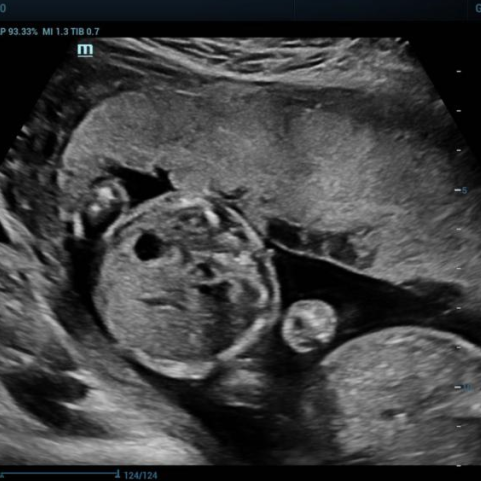

多年来,贵州航天医院各科室紧跟医学前沿,不断强技术、补短板,大力开展新技术、新项目,完成了许多高精尖、高难度、本地区“首例”的技术,填补了医院医疗技术空白,满足了群众日益增长的医疗需求。 复杂性双胎超声监护耗时耗力,技术难度大,风险高,为填补本地区复杂性双胎的超声监护技术空白,我院超声科在遵义市率先开展了此项技术,有效满足了双胎孕妇产检需求,保障了双胎新生儿的平安健康。 本期,我们将为大家带来超声科特色技术——复杂性双胎的超声监护。 案例分享 案例一 28岁的孕妇,自然受孕,怀有单绒毛膜双羊膜囊双胎(MCDA),在我院定期产检的过程中,孕32周超声检查发现两个胎儿的大脑中动脉血流流速(MCA-PSV)相差>0.7倍数的正常值(MoM),高度怀疑发生了双胎贫血红细胞增多序列征(TAPS)。为进一步明确诊断,产科立即组织超声科、手术室、新生儿科等科室进行多学科会诊(MDT),诊断为:双胎贫血红细胞增多序列征(TAPS),在征得孕妇及其家属的同意后,决定提前分娩,及时保障了两名胎儿的生命和健康。 双胎大脑中动脉血流 双胎贫血红细胞增多序列征(TAPS) 案例二 一名26岁的孕妇,是完全双角子宫,且为左侧子宫妊娠,怀有单绒毛膜双羊膜囊双胎(MCDA),一直在我院规律产检,孕16周时,超声检查发现双胎生长不一致,体重相差超过25%,考虑子宫畸形合并早发选择性胎儿宫内生长受限。孕妇在咨询相关上级医院专家后,得到减胎的建议,又前来我院咨询,在我院超声科和产科的合作下,查阅了大量文献、认真评估检查报告后,建议孕妇继续双胎妊娠。在规律、严密的超声监护下,双胎除体重差异外未出现严重胎儿并发症,在34周进行了分娩,截至目前,新生儿生长发育均正常。 胎儿生长曲线及子宫畸形三维重建 出生时体重差异 十月龄时 案例三 一名30岁的孕妇,自然受孕,怀有单绒毛膜双羊膜囊双胎(MCDA),在孕22周时超声检查发现双胎发生了选择性胎儿宫内生长受限,遂转诊到上级医院拟行胎儿镜治疗,但在行治疗的前一天,较小的胎儿在宫内发生死亡,在充分与孕妇及家属沟通后,要求继续妊娠,在定期规范的产检下,严密监测胎儿生长发育及胎儿颅脑MRI影像,最终在孕37周时通过剖宫产分娩,目前新生儿生长发育情况良好。 双胎之一胎死宫内(右图) 贵州航天医院自2021年开展复杂性双胎的超声监护以来,已服务大量双胎孕妇,集齐了所有单绒毛膜双羊膜囊双胎(MCDA)并发症病例,由经验丰富的超声医师进行此项检查,产科专业团队进行双胎的规范化监护和分娩,并与重庆医科大学附属第一医院建立了转诊通道,能够及时获得该院专家的指导和支持,为广大孕产妇提供优质、全面的医疗保障。 点击跳转贵州航天医院便民服务电话 什么是复杂性双胎的超声监护 “双胎”被称为产科之王,单绒毛膜双胎则为王中王,主要是因为单绒毛膜双羊膜囊双胎(MCDA)两胎儿共用一个胎盘,胎盘中存在血管吻合。 双胎妊娠的产前筛查及诊断主要依靠超声,相对于单胎妊娠,双胎妊娠并不是单胎检查的重复,双胎妊娠尤其是复杂性双胎的超声诊断更为重要的是关注双胎间循环的关联,双胎间生理及病理改变的相互影响,双胎间血流动力学监测及双胎间差异比较。 超声如何诊断 复杂性双胎并发症 在孕14周以前,超声要明确双胎的绒毛膜性:是单绒毛膜(MC)还是双绒毛膜(DC);孕10周前,可以通过孕囊的个数确定绒毛膜性;孕11周—14周,可以通过胎儿的性别、双胎之间隔膜的厚度、双胎儿分隔膜处胎盘的形态等来区分绒毛膜性。 双绒毛膜双胎的管理和单胎差不多,基本不需要增加超声检查的频次。单绒毛膜的管理相对谨慎,按照国际国内指南规范,单绒毛膜双胎自第16周起,每两周对双胎儿进行生长发育评估及血流检查。 复杂性双胎的超声监护,对超声医生技术要求较高,孕早期需对双胎的绒毛膜性进行精确判断;产科医生根据绒毛膜性制定孕期的产检计划;超声医生掌握胎儿宫内情况,及时与产科医生沟通,精确了解胎儿宫内安危后制定合适的治疗方案,给出适当的终止妊娠时机;复杂性双胎一般都面临早产的风险,所以新生儿团队的专业保障不可或缺,降低新生儿出生后的并发症及提高新生儿生活质量。复杂性双胎的较好妊娠结局,是通过孕期超声科、产科紧密合作,及新生儿出生后新生儿科管理多学科团队合作所获得的。 贵州航天医院超声科专家团队 吴艳辉 超声科 学科带头人 主任医师 专业擅长:从事超声诊断工作约30年,对心血管、小器官超声、超声引导下介入等具有丰富的临床经验。 骆科美 超声科 副主任医师 专业擅长:从事超声诊断工作33年,对胎儿心脏及颅脑、妇产超声诊断、盆底超声等诊断具有丰富的临床经验。 胡大海 超声科 副主任医师 专业擅长:从事超声工作17年,对心血管、外周血管、浅表器官超声诊断等具有丰富的临床经验。 刘 敏 超声科 副主任医师 专业擅长:从事超声诊断工作20余年,对妇产科超声、心脏血管超声诊断具有丰富的临床经验。 贵州航天医院超声科简介 贵州航天医院超声科配备多种超声检查设备(飞利浦彩超(IU-22、IU-Elite、HD11、Q5、Q7),迈瑞超声I9、DC-6、DC-8、GE-E8及床旁机,彩色超声诊断仪等),设有心血管诊室、妇产科诊室、腹部诊室、绿色通道、浅表小器官等检查室。 • ✦ 专科特色 ✦ • 四肢血管超声检查、双胎产前筛查及超声监护、超声造影检查技术、介入超声临床应用、经颅脑实质超声辅助筛查诊断帕金森病、女性性早熟超声诊断、盆底超声检查等。 NT超声检查 超声介入引导 肝脏超声造影 甲状腺造影 颅脑超声帕金森辅助检查 乳腺超声造影 上肢动静脉造瘘超声检查 双胎超声筛查 下肢血管超声检查 右心造影 • ✦ 诊疗范围 ✦ • 科室业务覆盖腹部、泌尿、妇科、产科(常规、NT筛查、III级筛查超声检查及高危妊娠监护)、成人心脏、外周血管、浅表器官(包含甲状腺、乳腺、阴囊、眼睛等)、颅脑(小儿颅脑、成人颅脑)、小儿肺超、造影、盆底、腹直肌、肌骨神经等检查及各种介入引导。